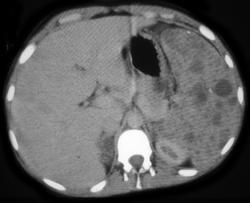

Ovarian Cancer With Implant in Pelvis & on the Spleen